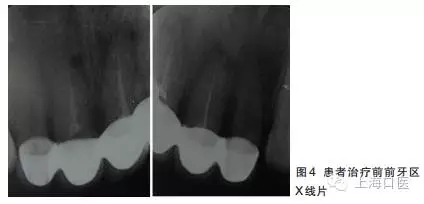

12~22烤瓷聯(lián)冠修復(fù),冠邊緣不密合,齦緣外形不協(xié)調(diào),牙齦紅腫,22烤瓷冠崩瓷。根管治療不完善,牙齦根尖部位有瘺管,X線影像顯示11、21根尖有陰影。

董艷梅教授:修復(fù)前如有以下情況,應(yīng)考慮進(jìn)行根管再治療:①X線片顯示前次根管治療不完善;②X線片顯示患牙根尖周新增病變或根尖周病變范圍擴(kuò)大或未見縮小;③患牙在前次根管治療后長期有癥狀或臨床體征。